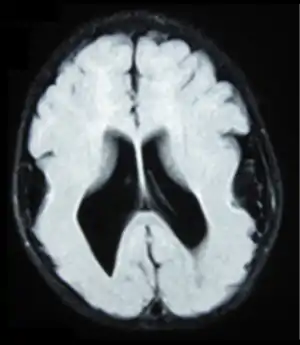

| Brain MRI, T1 weighted on a transversal plane, of an 8-month old boy with lissencephaly. Note the scarce and wide gyri, mostly on the parietal, temporal and occipital lobes, the absence of a true Sylvian fissure, and the augmented thickness of the gray matter. The boy had a severe developmental delay and seizures. | |